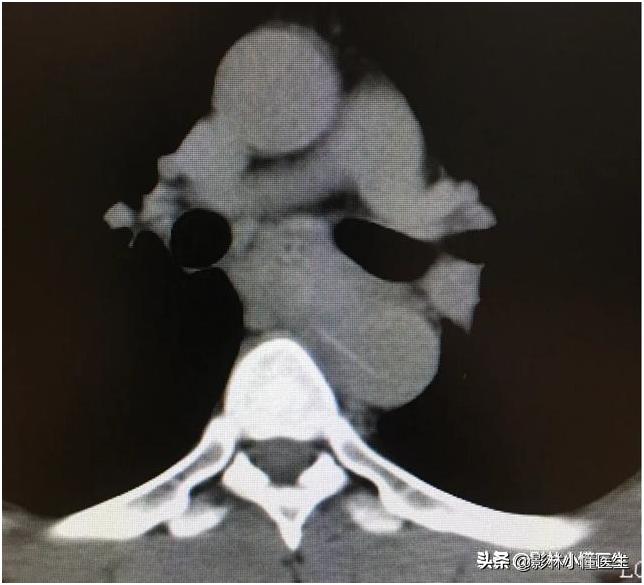

例2

鱼刺刺穿食管及主动脉壁,治疗费用高、预后极差。